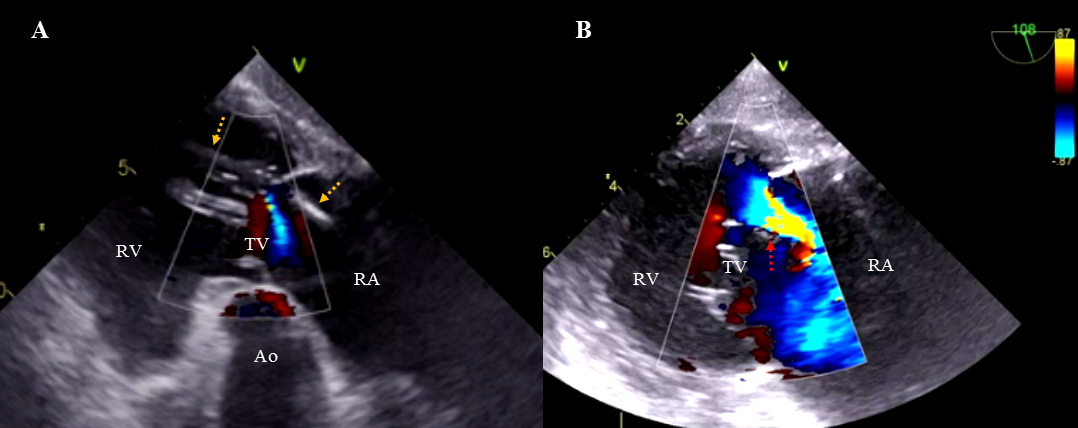

Background: Changes in tricuspid valve (TV) function following

transvenous lead extraction (TLE) and their impact on long-term survival have not

yet been investigated. Methods: From 3633 patients undergoing lead

extraction between 2006 and 2021, TV function before and after TLE was evaluated

in 2693 patients. Results: After TLE, the TV function remained unchanged

in 82.36% of patients, worsened in 9.54%, and improved in 8.10%. Abandoned

leads (odds ratio, OR = 1.712; p = 0.044), fibrotic adhesions between leads and TV

apparatus (OR = 3.596; p